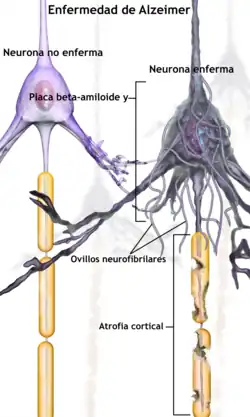

Esta observación apoya la hipótesis tau, la cual defiende que es esta proteína la que da inicio a la cascada de trastornos de la enfermedad de Alzheimer.[57] De acuerdo con este modelo, las tau hiperfosforiladas adoptan formas anómalas, distribuyéndose en largas hileras. Eventualmente forman ovillos de neurofibrillas dentro de los cuerpos de las células nerviosas.[75]

Cuando esto ocurre, los microtúbulos se desintegran, colapsando el sistema de transporte de la neurona. Ello puede dar inicio a las primeras disfunciones en la comunicación bioquímica entre una neurona y la otra y conllevar la muerte de estas células.[76]

La neurodegeneración en la enfermedad de Alzheimer se debe a dos procesos: en el primero interviene la proteína beta-amiloide, que se acumula formando placas en el exterior de las neuronas. A su vez, se produce una alteración en el comportamiento de la proteína tau, que comienza a formar fibras entretejidas dentro de la célula nerviosa, los llamados ovillos. Es probable que muchos individuos, en su vejez, desarrollen estas placas y ovillos como parte del proceso normal de envejecimiento. Sin embargo, los pacientes con alzhéimer tienen un mayor número en lugares específicos del cerebro, como el lóbulo temporal.[83]

La enfermedad de Alzheimer se considera, debido a la agregación anormal de la proteína tau, como una tauopatía. Las neuronas sanas están compuestas por citoesqueleto, una estructura intracelular de soporte, parcialmente hechas de microtúbulos. Estos microtúbulos actúan como rieles que guían los nutrientes y otras moléculas desde el cuerpo neuronal hasta los extremos de los axones y viceversa. Cada proteína tau estabiliza los microtúbulos cuando es fosforilada y por esa asociación se le denomina proteína asociada al microtúbulo. En el alzhéimer, la tau debido a cambios químicos que resultan en su hiperfosforilación, se une con otras hebras tau creando ovillos de neurofibrillas y de esta manera, desintegra el sistema de transporte de la neurona.[89]